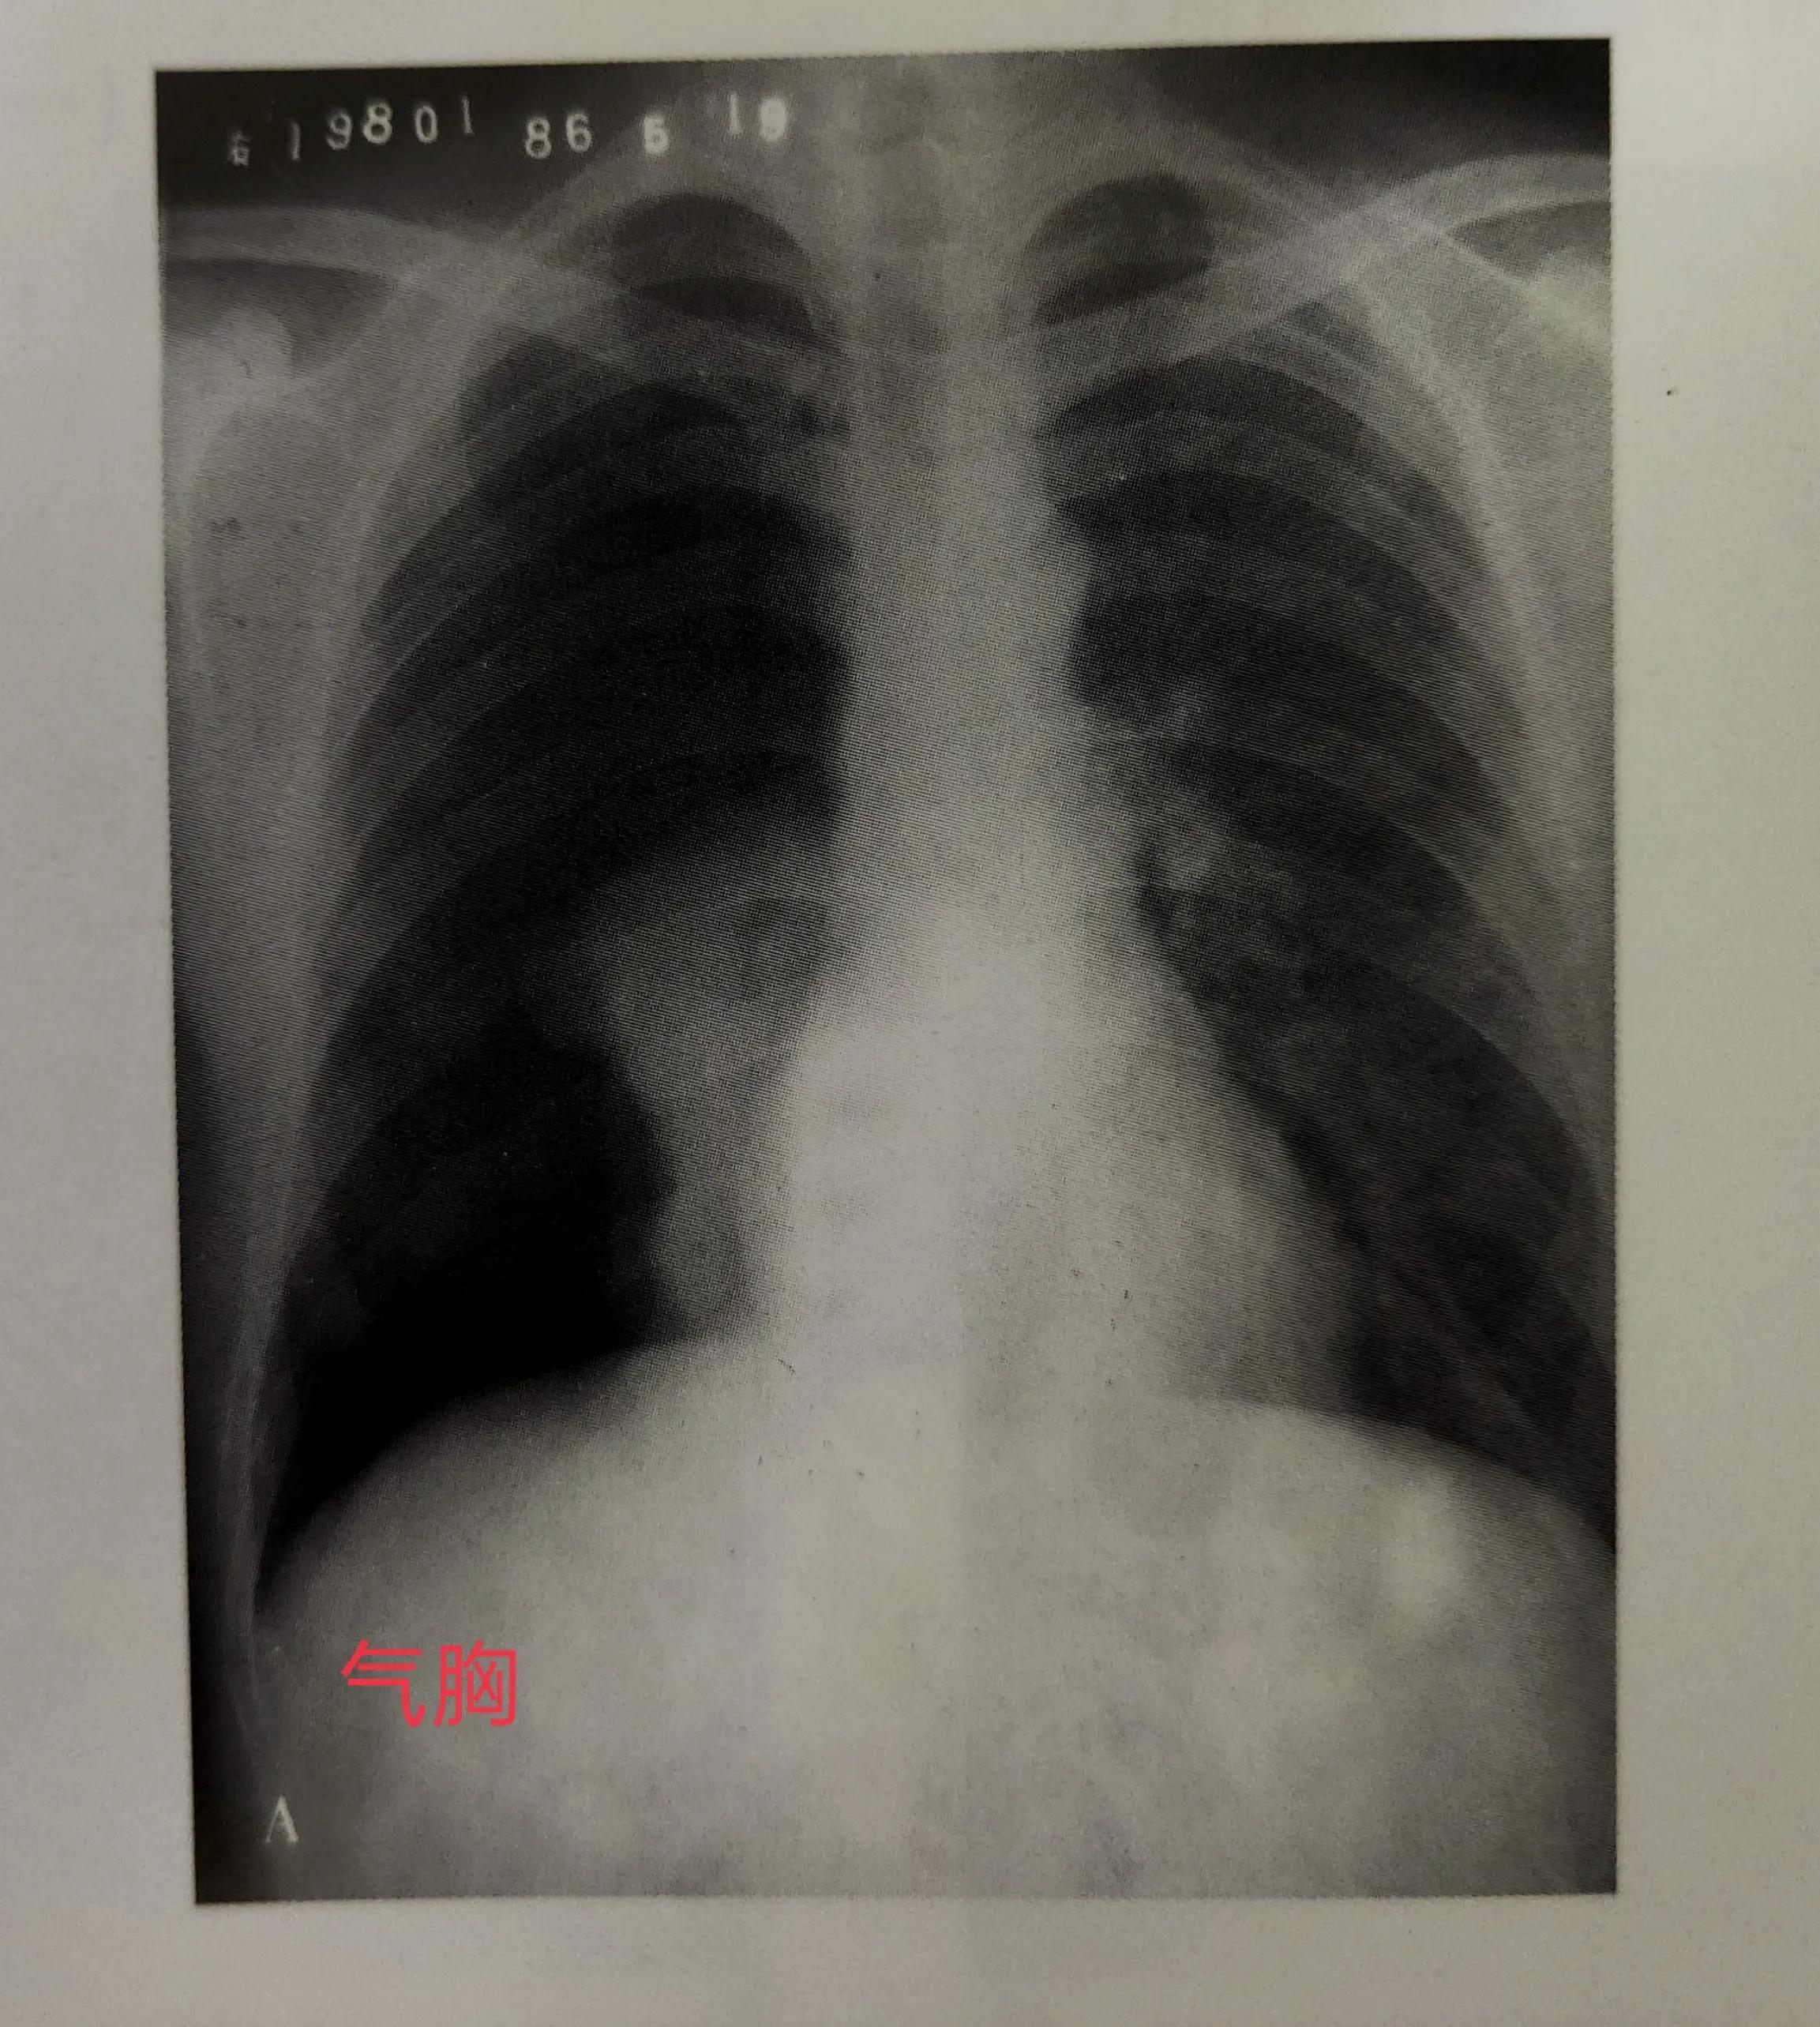

在X线片上呈现的黑白灰等差别,可做四种密度:我们在片子上看到的白色的,是高密度,就是我们的骨头或钙化灶,如股骨、颅骨。我们看到的灰白色的,是中等密度,是我们的软骨、肌肉、神经、实质器官、结缔组织及体液。我们在片子上还能看到灰黑色的,这个是较低密度,是我们的脂肪组织。最后X线片上看到的黑色,是低密度,是气体,比如拍的胸片,如果是一大片黑,那很有可能是气胸了。